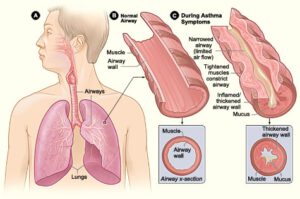

Asthma

Cheatsheets

1

Mnemonics

0

Images

1

Picmonic

0